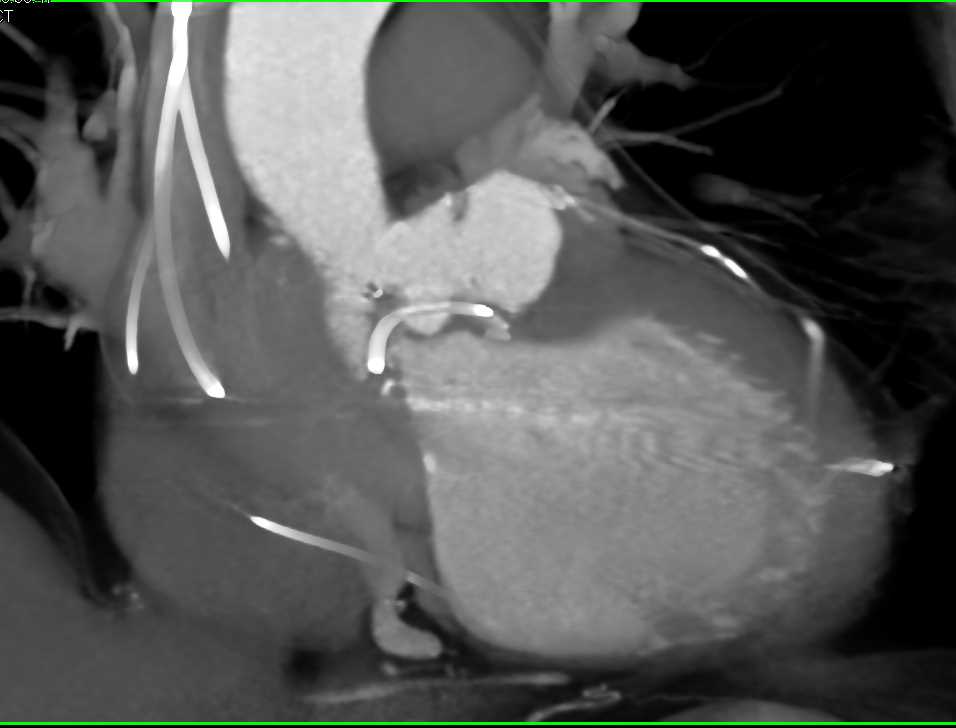

Metastatic Melanoma to the Adrenals and Lung